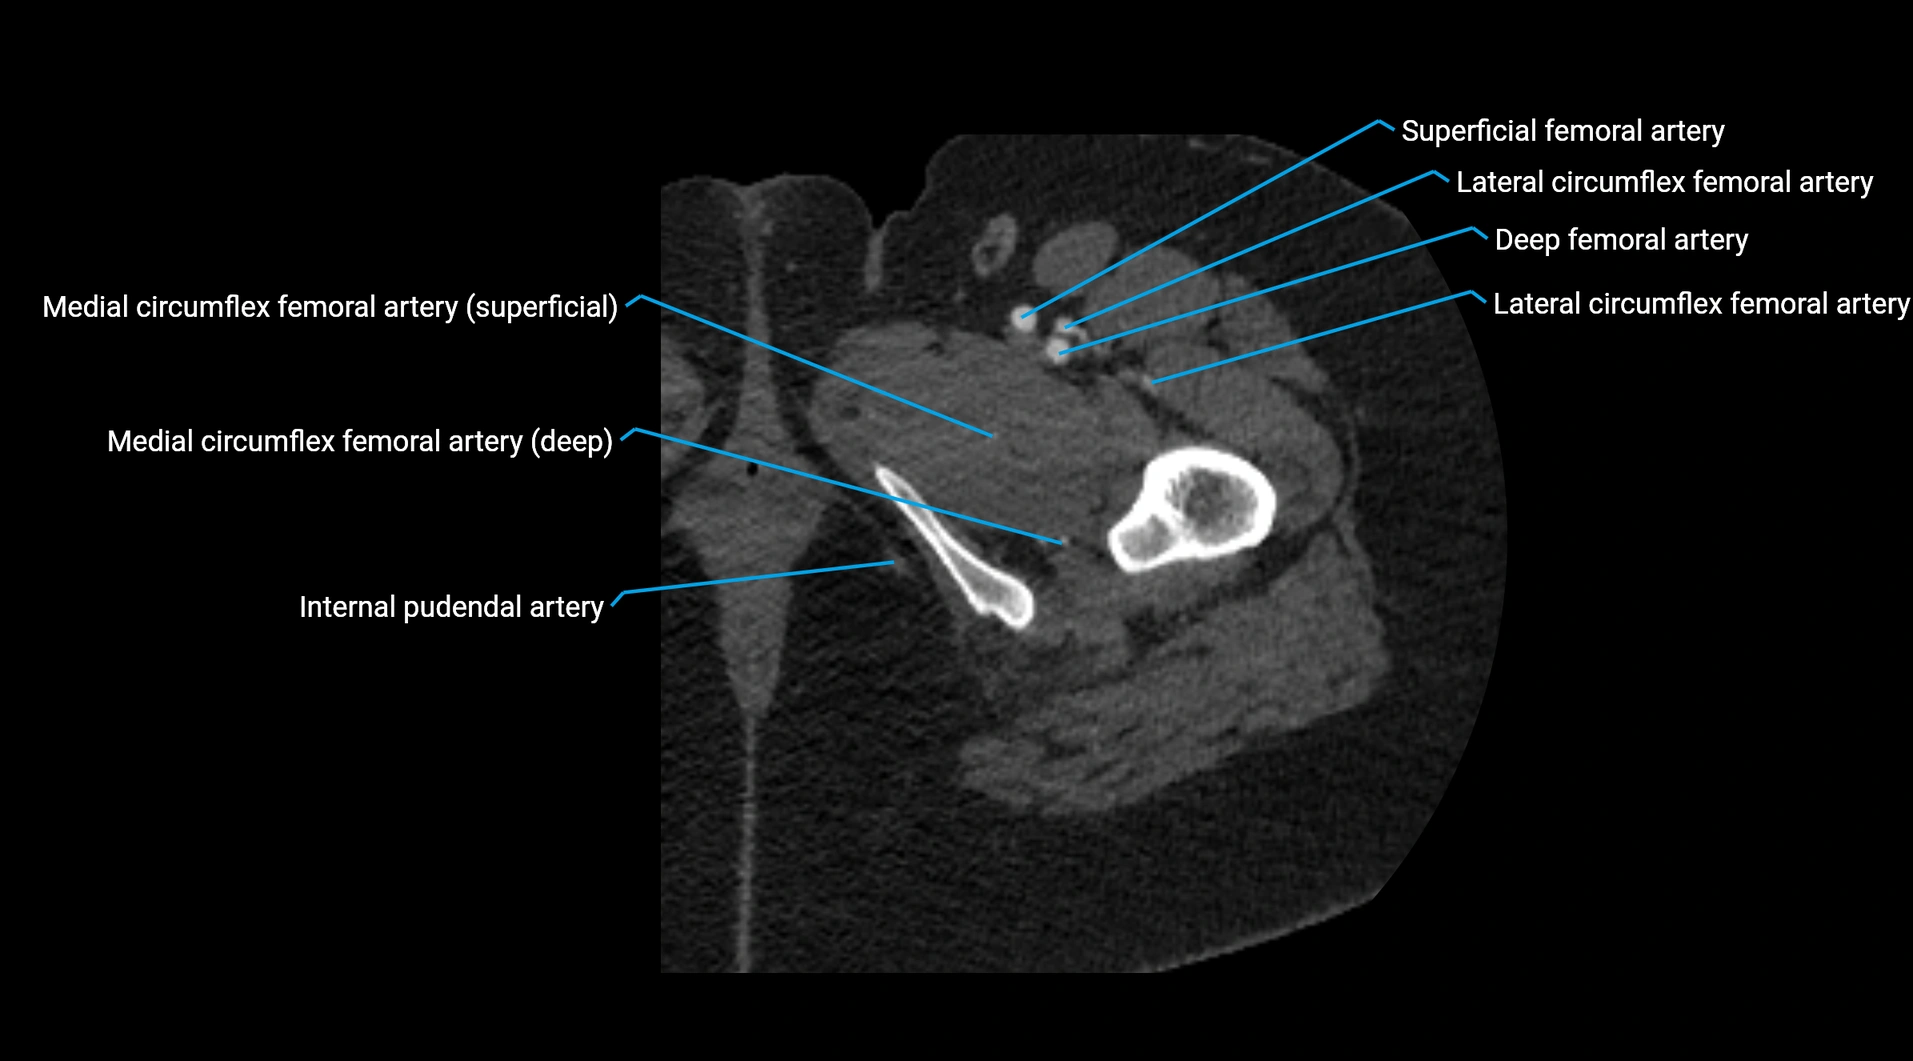

CT images

image

Contrast-enhanced CT (CTA):

• Gold standard for abdominal aortic imaging

• Provides excellent detail of lumen, wall, aneurysm, thrombus, and branch vessels

• Multiplanar and 3D reconstructions help in aneurysm measurement, stent graft planning, and dissection evaluation